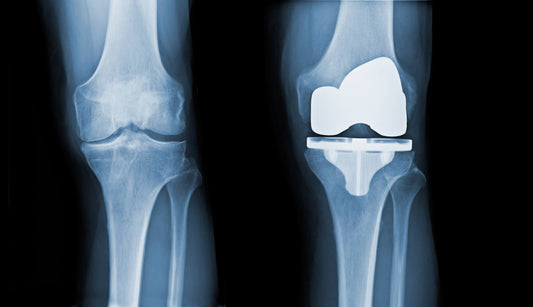

How Long Does a Knee Replacement Last? The 25-Year Answer & The Critical Factor Your Surgeon May Not Mention

Landmark Lancet study reveals 82% of knee replacements last 25 years. Discover why the replacement is only half the story and how underlying biomechanics may influence long-term success.